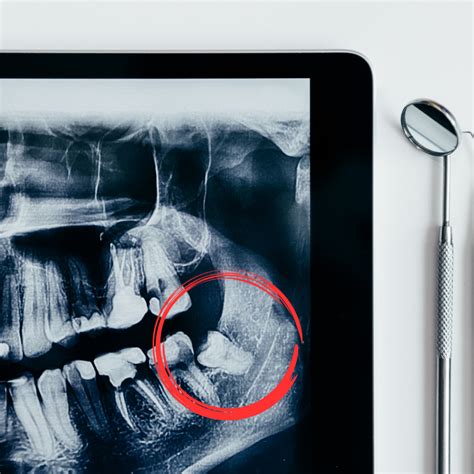

Recomendamos realizar primero una exploración con un odontólogo o dentista especializado en cirugía oral. Este especialista realizará una ortopantomografía para visualizar la posición de las muelas del juicio, la forma de sus raíces, y su relación con el nervio dentario inferior.